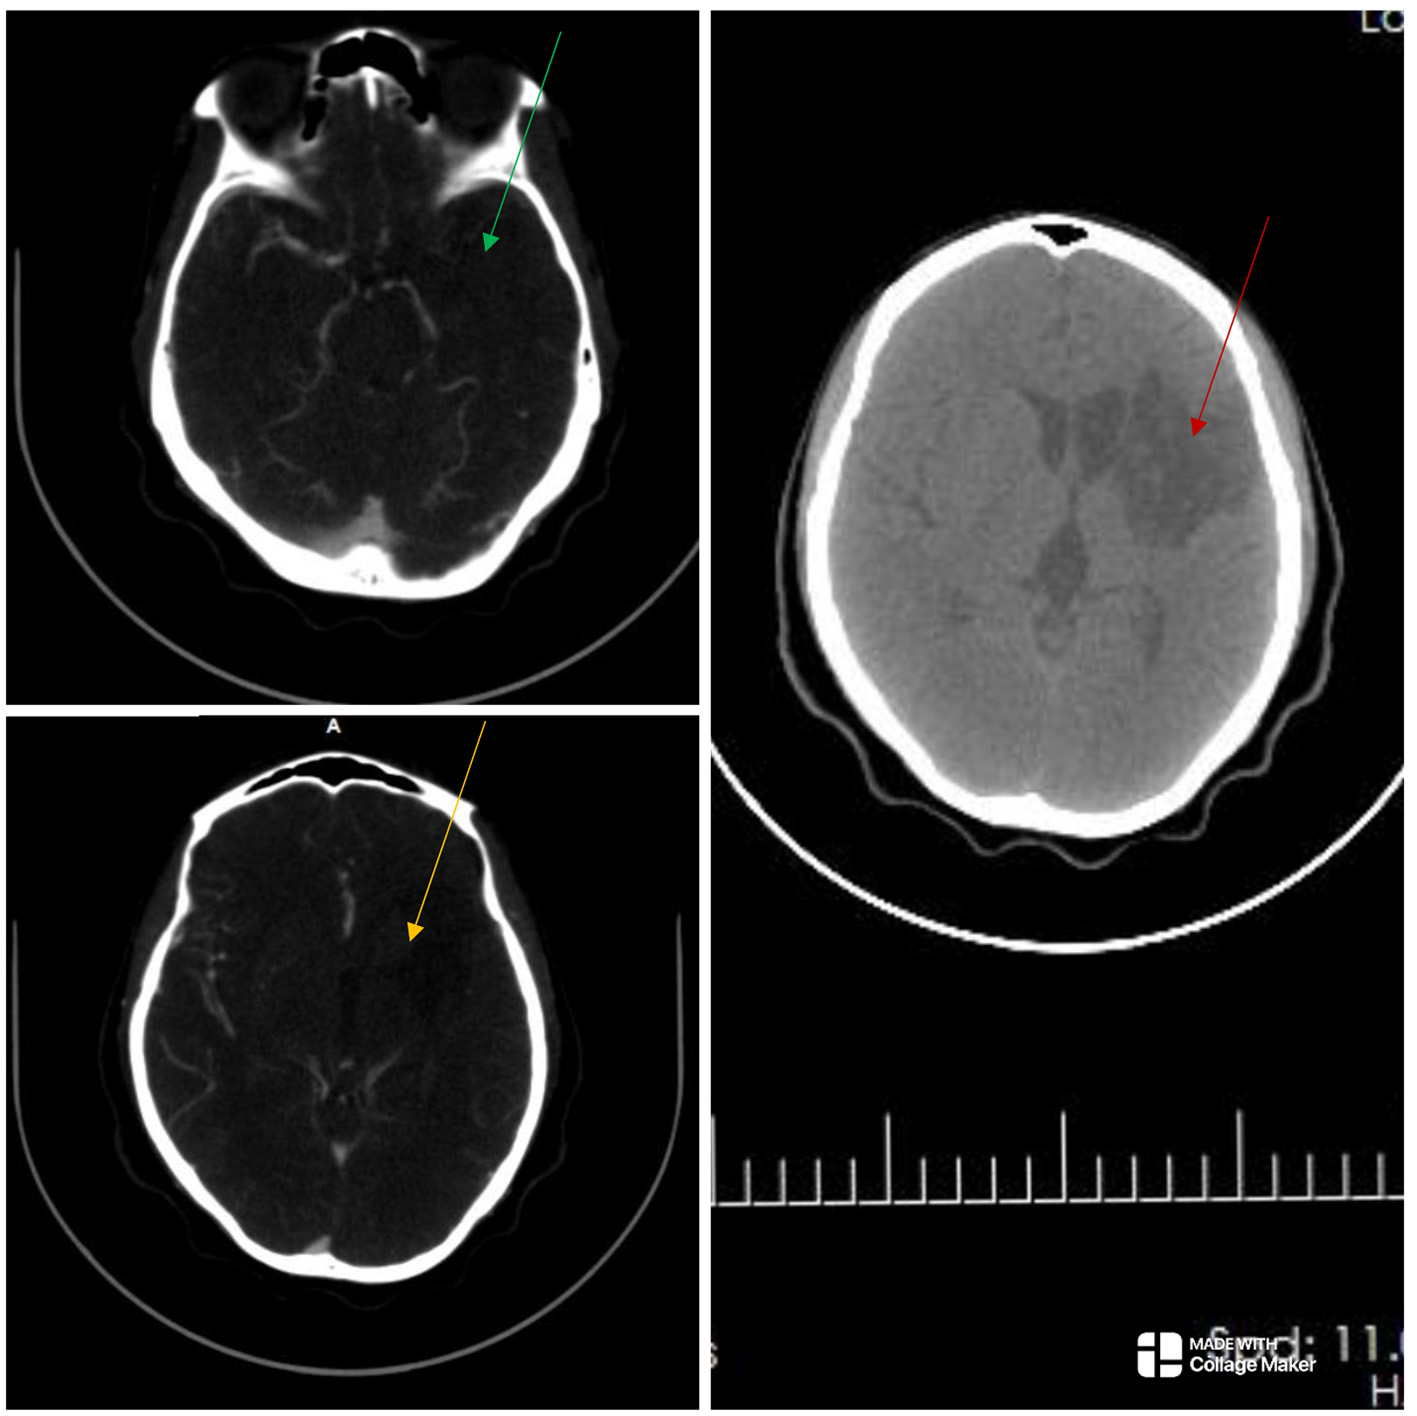

The electrocardiogram and echocardiogram were normal. Other laboratory findings are shown in Table 1. The carotid Doppler Ultrasonography (USS) showed complete occlusion of the left common carotid artery and left internal and external carotid arteries with absent flow on Doppler interrogation (Figure 1). The cranial CT scan (Figure 2) showed an ill-defined, oval-shaped hypodense area (HU = 14–36) involving the left basal ganglia and frontal lobe in keeping with an acute infarct. The brain CTA showed diffuse enhancing aortic arch wall thickening and multiple aortic arch branch obstructive disease (Figure 2). There were multiple smooth-walled, long-segment luminal stenoses but no aneurysms. Overall features showed diffuse vascular smooth muscle wall disease of both intracranial and extracranial vessels, in keeping with inflammatory vascular disease.

Figure 2

The cranial computed tomography (CT) scan (right) shows an ill-defined oval-shaped (red arrow), hypodense area (HU = 14–36) involving the left basal ganglia and frontal lobe in keeping with an acute infarct. The CT angiography (left) showed absent opacification at the origin of the right common carotid artery and a string-like lumen from C7/T1 to C4/5 (not shown). There was opacification at the origin of the left internal carotid artery (ICA) but the artery abruptly terminated just beyond that point. There was no opacification in the cervical or intracranial segments of the left ICA (green and yellow arrows), as well as in the left subclavian artery. There were short segment stenoses in the pulmonary artery branches bilaterally (not shown). Overall features showed diffuse vascular smooth muscle wall disease affecting both intracranial and extracranial vessels, in keeping with inflammatory vascular disease.